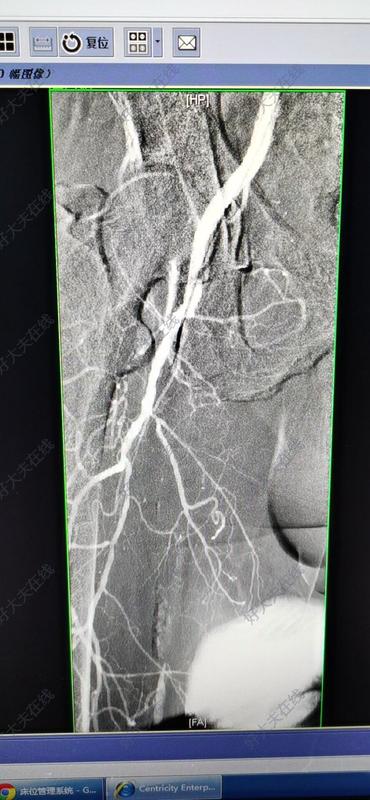

下肢动脉疾病血管成形术和支架置入术的ABC经皮腔内血管成形术(percutaneoustransluminalangioplasty,PTA)领域的进展导致其在复杂病变中的应用范围扩大。主要技术为球囊血管成形术;但下肢动脉常发生再狭窄。因此,常采用支架置入术来改善治疗效果并达到长期通畅。改善PTA结果的最新工具是药物洗脱支架和球囊,它们可减少新生内膜增生的发生。结果优于传统的球囊扩张或裸金属支架。背景信息外周动脉疾病(PAD)通常是由供应下肢的主要血管的动脉粥样硬化引起的。约10%的世界人口患有外周动脉疾病。大多数PAD患者无症状。然而,一些PAD患者的行走能力有限,因此生活质量降低。在药物治疗无效的情况下,或在严重的PAD病例中,需要血管内和外科干预。不同的血管内技术可用于治疗周围血管狭窄和/或闭塞。除了传统的普通球囊血管成形术(POBA)之外,标准的介入治疗方案还有药物涂层球囊(DCB)、裸金属支架(BMS)和药物洗脱支架(DES),以及许多斑块切除术装置。此外,与POBA相比,支架置入术可以提高通畅率,可能也可以提高DCB的通畅率;因此,它经常被使用,特别是在长病变和/或钙化病变。下肢动脉疾病(LEAD)大多数LEAD患者无症状。必须评估行走能力以检测临床隐匿性LEAD。即使是无症状的LEAD患者也是心血管事件的高危人群,将受益于大多数心血管事件预防策略,特别是严格控制危险因素。有症状的LEAD患者适用抗血栓治疗。无症状患者使用这些药物未证实有益。在做出治疗决定之前,解剖影像学检查的数据应与症状和血流动力学检查结合分析。早期识别组织缺损和/或感染是重要的,通过多学科方法进行保肢必须转诊至血管专科医师。伴有神经功能缺损的急性肢体缺血要求紧急血运重建。间歇性跛行的管理策略一些研究已经证明了血管内治疗和开放手术对缓解跛行症状和生活质量(QOL)的疗效。然而,这些干预措施的持久性有限,并且可能与死亡率和发病率相关。因此,它们应该仅限于对药物治疗没有良好反应的患者,或当致残性症状大大改变日常生活活动时。一项系统综述纳入了十多项项试验(超过一千五百例患者),比较了药物治疗、血管腔内治疗和开放手术在跛行患者中的疗效,结果显示,与前者相比,其他方案均与跛行症状和生活质量的改善相关。与腔内治疗相比,开放手术可能与更长的住院时间和更高的并发症发生率相关,但可获得更持久的通畅率。间歇性跛行的血运重建对于间歇性跛行患者,心血管病预防和运动训练是治疗的基石。如果日常生活活动严重受损,可建议进行血运重建和运动疗法。动脉病变的解剖位置和范围对血运重建方案有影响。主髂动脉病变孤立的主髂动脉病变是跛行的常见原因。对于髂动脉短段狭窄/闭塞(<5cm)的患者,腔内治疗具有良好的远期通畅率(5年以上>90%)和低并发症风险。髂股动脉病变适用复合手术,通常是股动脉内膜切除术或旁路术联合髂动脉腔内治疗,即使是长时间闭塞。如果闭塞延伸至肾下主动脉,则可考虑对主动脉分叉进行覆膜血管内重建。术后1年和2年的一期通畅率分别为87%和82%。如果闭塞包括主动脉至肾动脉和髂动脉,则主动脉-股动脉旁路手术适用于严重的生命受限性跛行患者。在这些广泛病变中,血管内治疗可能是一种选择,但它并非没有围手术期风险和长期闭塞股腘动脉病变股腘动脉病变在跛行患者中较为常见。如果股深动脉的循环正常,有监督的运动训练很有可能缓解跛行;干预大多是不必要的。如果需要血运重建,血管腔内治疗是<25cm狭窄/闭塞的首选治疗。如果闭塞/狭窄为>25cm,血管腔内再通仍有可能,但手术旁路可获得更好的长期通畅性,特别是使用大隐静脉(GSV)时。血管腔内治疗的挑战是股腘动脉区域内支架的长期通畅性和耐用性,该区域的动脉活动度大(因关节的活动)。一些新的血管腔内解决方案(如斑块切除术装置、药物洗脱球囊和新型支架设计)已被证明可提高远期通畅率。膝下动脉疾病扩大的膝下动脉病变主要见于糖尿病患者,常合并股浅动脉(SFA)病变(流入道病变)。在狭窄病变和短段闭塞病变中,血管腔内治疗可作为首选。在小腿动脉长时间闭塞的情况下,自体静脉旁路术可获得较好的长期通畅率和腿部存活率。如果患者的手术风险增加或没有自体静脉,可以尝试血管腔内治疗。对于小腿动脉流出道闭塞,现在已经开发出下肢远端深静脉动脉化的全腔内微创技术,即LimFlow系统,一种自膨覆膜支架系统)可绕过腿部和足部永久阻塞的动脉,并通过静脉将氧合血输送回足部。恢复下肢灌注可能有助于缓解慢性疼痛,提高生活质量,促进伤口愈合,并预防大截肢。慢性肢体重度缺血(CLTI)慢性肢体重度缺血指定了与若干因素相关的易损肢体存活的临床模式。根据缺血、伤口和感染的严重程度对风险进行分层。这里的治疗是紧急的,以避免失去肢体,尽管一些患者可以保留他们的腿很长时间,即使没有血运重建。慢性肢体重度缺血患者的管理所有CLTI患者必须接受矫正危险因素的最佳药物治疗(BMT)。在糖尿病患者中,血糖控制对于改善肢体相关结局尤其重要,包括降低大截肢率和提高膝下血运重建后的通畅率。血运重建应尽可能地进行血运重建。BASIL随机试验,直接比较了CLTI患者的血管腔内治疗和开放手术。2年时,在无截肢生存率方面,血管腔内治疗和外科手术无显著差异。在2年后的幸存者中,旁路手术与生存率和无截肢生存率的改善相关。这些数据受到最新血管腔内治疗技术的挑战。迄今为止,药物洗脱球囊在膝下疾病的治疗中并未显示出优于POBA的效果。在CLTI患者中设计良好的前瞻性研究和随机对照试验很少。这可能与以下事实有关:由于CLTI的发病率低于轻度PAD,因此在这一特定人群中开展研究并不容易,以及CLTI患者的随访问题。同时,在每个解剖区域,两种血运重建方案应单独讨论。主髂动脉疾病CLTI几乎从不与孤立的主髂动脉病变相关,常伴有下游病变。完整的数字减影血管造影(DSA)或CT动脉成像(CTA)至足底弓常常是必要的,以便进行适当的动脉网络评估和手术规划。必要时应鼓励采用一步法进行杂交手术(例如主髂动脉支架置入和远端旁路)。股腘动脉疾病CLTI不太可能与孤立的股浅动脉(SFA)病变有关;股腘动脉受累常合并主髂动脉或膝下动脉病变。在多达40%的病例中,需要进行流入道治疗。应根据病变的复杂程度设计血运重建策略。如果首先选择血管腔内治疗,则应保留潜在旁路移植物的吻合区。在决定搭桥手术时,应尽量缩短搭桥时间,使用大隐静脉。血管腔内模式虽然目前已有多种血管腔内治疗方法,但尚未就特定类型治疗的优越性达成明确共识。球囊血管成形术长球囊的引入使经皮腔内血管成形术(PTA)得以广泛应用,包括长病变和弥漫性病变,特别是考虑到PAD通常是多平面和多支血管的特性。PTA治疗SFA和膝下动脉的初始成功率为90%。然而,血管长期通畅性是一个问题,在12个月随访时,60%以上的病例发生再狭窄。药物洗脱球囊几项研究已经证实,在股腘动脉疾病的一期通畅方面,药物洗脱球囊(DEB)与PTA相比有益。据报道,使用紫杉醇涂层球囊(PCB)时,靶病变血运重建(TLR)的发生率较低。LEVANTⅱ试验是一项高功效的54个中心的随机对照试验,纳入了476例有症状的间歇性跛行或缺血性疼痛(在静息状态下)和血管造影显示显著动脉粥样硬化的患者,结果显示接受PCB的血管成形术患者的初级通畅率高于接受PTA的患者,12个月时的安全性结果不劣于接受PTA的患者。然而,各组的TLR和功能结局(如再次干预率、血栓形成率和截肢率)相似。THUNDER试验的5年结果表明,与PTA相比,PCB的TLR发生率较低,两组不良事件、截肢率和死亡率差异无统计学意义。支架与PTA相比,自膨式镍钛合金裸金属支架(BMS)可改善股腘动脉疾病患者的预后,即使是在有多种合并症的复杂患者中。一项荟萃分析纳入了接受球囊扩张和自扩张BMS治疗膝下疾病的患者,结果显示12个月期间的血管造影结果、通畅率和临床结局均令人满意。ZilverPTX试验表明,对于SFA疾病,紫杉醇洗脱支架的5年一期通畅率高于PTA或临时BMS。临床试验数据显示,与PTA或BMS相比,药物洗脱支架(DES)治疗膝下疾病的通畅率显著提高。纳入200例膝下疾病患者的ACHILLES试验表明,西罗莫司洗脱支架(SES)的一期通畅率较高和较低的TLR发生率。影响PTA疗效的因素分析PTA的成功与否取决于PAD的严重程度、类型(狭窄或闭塞)、病变长度、血管质量、伴随疾病(糖尿病或冠心病)以及持续存在的危险因素(吸烟、血压、透析)。病变可能在腹股沟上(即累及主动脉和髂动脉)、股腘动脉或膝下。PTA对髂动脉病变的疗效最好,对远端血管的疗效逐渐下降。一项包含6项研究的荟萃分析报告,主髂动脉闭塞性疾病PTA和支架置入术的即刻技术成功率为96%,比单纯PTA的成功率更高。裸金属镍钛合金支架治疗症状性股腘动脉PAD患者12个月的临床疗效可接受,且受临床和病变特异性特征的影响。在不同研究的荟萃分析中,12个月的通畅率为69.8%。对于慢性严重肢体缺血(CLI)患者,应保留膝下动脉PTA和支架置入术。尽管如此,对于患者何时应该接受支架尚无真正的共识。一项随机对照试验的系统综述和荟萃分析显示,与球囊血管成形术和BMS相比,膝下动脉置入药物洗脱支架与显著较低的再狭窄、TLR和截肢率相关,并改善伤口愈合。杂交手术与治疗多节段慢性外周动脉疾病的良好长期结果相关。糖尿病仍然是预后较差的决定因素,而疾病的严重程度和既往同侧血运重建与较差的保肢效果相关。LEAD血管腔内治疗后的抗血栓药物尽管越来越多的患者因进行性PAD而接受血管腔内支架治疗,但关于介入治疗后的管理,特别是双重抗血小板治疗(DAPT)的知识仍然非常有限。目前建议在介入治疗后至少使用1个月的DAPT,不论支架类型(裸金属还是药物洗脱)。膝下动脉支架置入术后通常需要较长时间的DAPT,但目前尚无具体证据。对经皮腹股沟下血运重建后的抗凝治疗进行的一项前瞻性测试。血管通畅率无改善,出血明显增加。几项研究调查了4~6周DAPT治疗方案12个月后外周动脉支架置入的结局。复杂病变支架置入术后再干预率为14.2%~28.3%。此外,药物涂层支架研究显示再干预率低,MAJESTIC试验(单组)的TLR为4%,ZilverPTX试验的TLR为9.5%。在有症状的外周动脉疾病患者中,在减少心血管事件方面,替格瑞洛未显示优于氯吡格雷。两组患者的大出血发生率相似。在冠状动脉疾病(CAD)患者中,无论临床表现如何,共存LEAD均与较差的预后相关。CAD患者合并LEAD可能是延长DAPT的理由。PRODIGY试验检验了急性冠脉综合征(ACS)后的DAPT持续时间。在LEAD患者中,延长DAPT(24个月)与短DAPT(6个月)相比降低了主要疗效终点(由死亡、MI或脑血管意外构成的复合终点)的风险。显著的交互作用提示仅在合并LEAD的患者中有特定的获益。PEGASUS-TIMI54试验研究了既往有心肌梗死(1~3年)的病情稳定患者在小剂量阿司匹林基础上加用替格瑞洛(90mg,每日2次或60mg,每日2次)。在已知LEAD患者(占整个人群的5%)中,替格瑞洛显著降低了肢体主要不良结局(急性肢体缺血和外周血运重建)的风险。因此,对于既往有心肌梗死史(<3年)的LEAD患者,可考虑在小剂量阿司匹林的基础上长期应用替格瑞洛。对于接受腹股沟下经皮血运重建的LEAD患者,既往有急性冠脉综合征病史(<1年)和/或经皮冠状动脉介入治疗(PCI)史时,DAPT可延长至1个月以上。需要长期口服抗凝治疗的LEAD患者的抗血栓治疗对于有口服抗凝(OAC)适应证的LEAD患者,支持特定抗血栓治疗方案的证据很少。ROCKET-AF试验的事后分析报告,LEAD患者接受利伐沙班或华法林治疗与无LEAD患者相比,在严重和非严重临床相关出血方面存在显著的交互作用。联合治疗的持续时间应尽可能有限(1个月),具体取决于临床适应证和出血风险。加用抗血小板治疗可能取决于合并CAD和对LEAD血管腔内血运重建的需求。除了膝下支架置入或血栓形成风险非常高的复杂病变外,三联疗法(即阿司匹林、氯吡格雷和一种抗凝剂)不鼓励在这种情况下使用。总而言之,目前外周血管介入治疗包括各种可能改善PAD临床结局的技术。DEB的使用提高了股腘动脉和膝下动脉PAD的通畅率和TLR结局。支架置入术在挽救肢体和主要干预措施中扮演着越来越重要的角色,随着DES的发展,支架置入术尤其具有前景。需要进一步设计良好和高功效的试验来确定PAD患者管理的理想治疗策略。